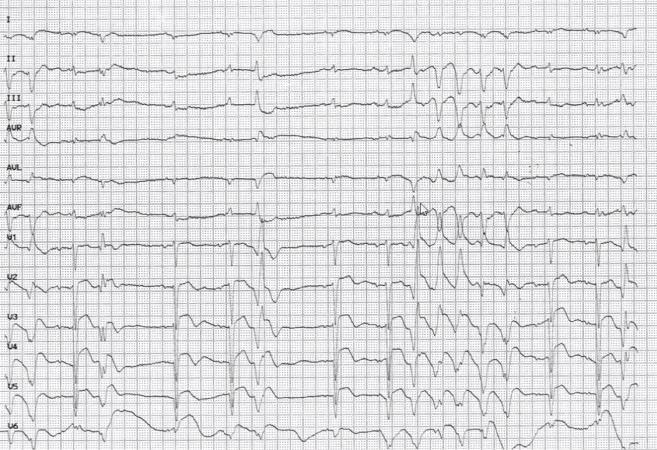

辅助检查:心电图 V1-V6QS型,ST段抬高0.1-0.3mv(见图1)